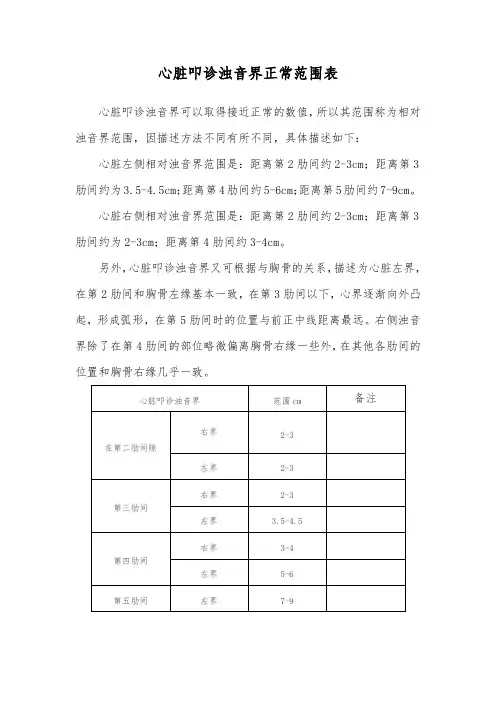

心脏叩诊浊音界正常范围表

心脏叩诊浊音界可以取得接近正常的数值,所以其范围称为相对浊音界范围,因描述方法不同有所不同,具体描述如下:心脏左侧相对浊音界范围是:距离第2肋间约2-3cm;距离第3肋间约为3.5-4.5cm;距离第4肋间约5-6cm;距离第5肋间约7-9cm。

心脏右侧相对浊音界范围是:距离第2肋间约2-3cm;距离第3肋间约为2-3cm;距离第4肋间约3-4cm。

另外,心脏叩诊浊音界又可根据与胸骨的关系,描述为心脏左界,在第2肋间和胸骨左缘基本一致,在第3肋间以下,心界逐渐向外凸起,形成弧形,在第5肋间时的位置与前正中线距离最远。

右侧浊音界除了在第4肋间的部位略微偏离胸骨右缘一些外,在其他各肋间的位置和胸骨右缘几乎一致。

正常成人左锁骨中线距离前正中线的距离为8-10cm。

心脏左界第二肋间处相当于肺动脉段,第三肋间为左心房耳部,第四五肋间为左心室,心脏右界第二肋相当于上腔静脉和主动脉升部,自从第三肋间以下为右心房。

心浊音界的大小、形态和位置可以因为心脏病变以及心外因素的影响而改变。